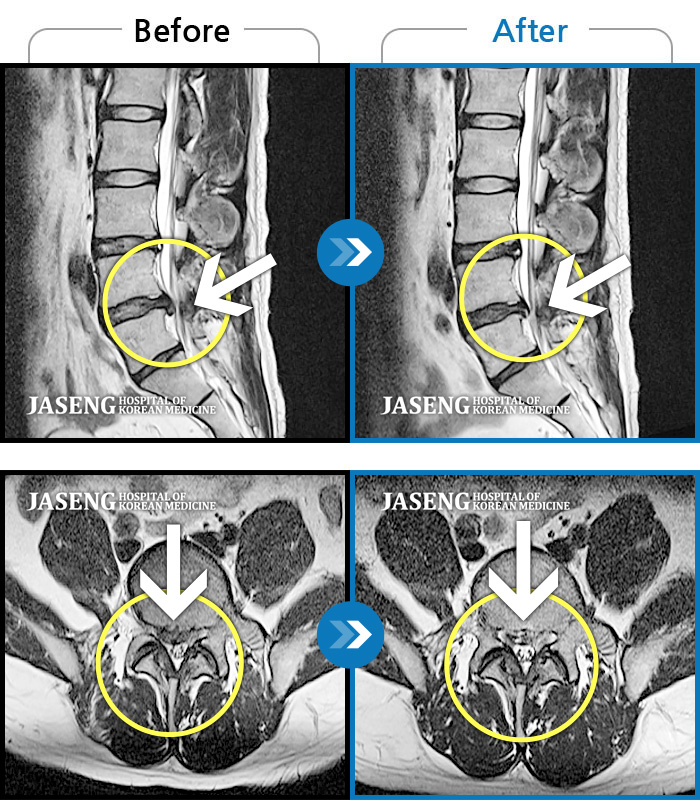

MRI 치료사례

오른쪽 종아리 당김